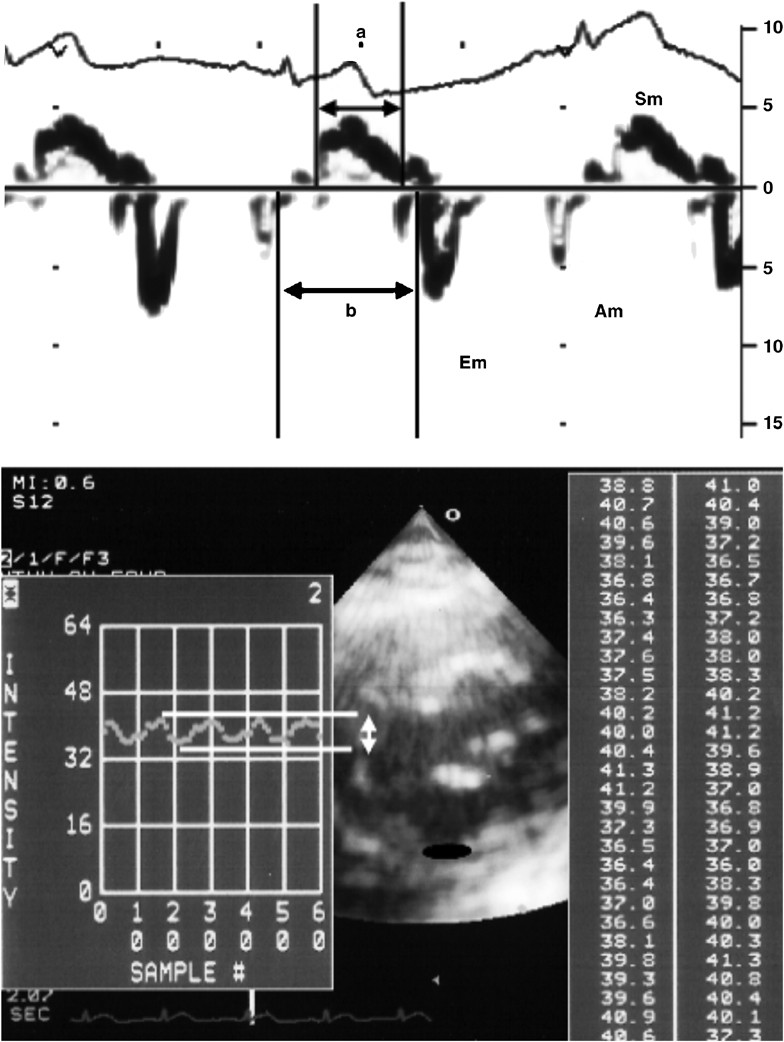

images of Imaging Current ... for Emerging Technologies Cardiovascular and